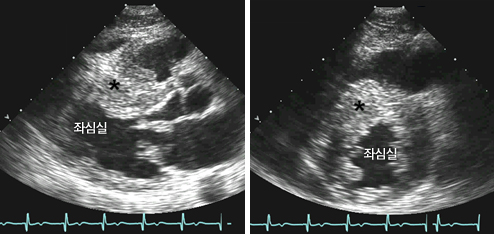

신체검사에서 좌심실 유출로의 폐색이 동반된 환자에서는 심첨 박동이 2개 또는 3개로 나타나는 것이 특징적이며, 이는 심실 수축과 항진된 심방 수축 그리고 이완 초기의 좌심실 충만에 의해 나타난다. 신체검사에서 심잡음이 청진되는 경우가 흔한데, 좌심실 유출로의 폐색이 동반된 환자에서는 수축기 잡음이 흉골좌연을 따라 청진된다. 또 그 소리 크기가 환자의 자세, 발살바법, 운동 등에 따라 다양하게 변화되는 것이 특징이다. 심첨부에서 범수축기잡음이 청진될 수도 있는데 이는 동반된 승모판 역류증에 의한 것이다. 좌심실 유출로 폐색이 있는 환자에서는 경동맥파가 두 개로 관찰된다. 그러나 좌심실 유출로 폐색이 없는 환자에서는 이런 특징적 신체검사 소견이 거의 동반되지 않는다. 95%의 환자에서 심전도 이상 소견을 보이고, 증상이 없는 가족에서도 심전도 이상이 흔히 관찰된다. 좌심실 비대, ST-T 변화, 좌심방 확장, 깊고 얇은 Q파, 외측유도에서 R파의 감소 등이 대표적이다. 하지만 어떤 심전도 소견도 향후 심혈관계 사건을 예측하는 데는 유용하지 못하다. 비후성 심근증의 진단에 가장 유용한 검사는 심초음파 검사로 특징적인 비대칭적 심실중격 비후나 심첨부 비후가 관찰되고 승모판막의 수축기 전방 이동과 그로 인한 좌심실 유출로의 폐색, 승모판 역류증과 같은 다양한 소견을 관찰할 수 있다. 또한 환자의 심부전 증상을 유발하는 좌심실의 이완 기능을 평가하는 데 있어서도 심초음파는 매우 유용하다. 최근 심장 자기공명영상(MRI), 심장 컴퓨터 단층촬영(CT)의 발전으로 비후성 심근증의 진단에 있어 도움이 된다.

심실중격 비후성 심근증의 심초음파: 심실중격(*)이 좌심실 후벽에 비해 두꺼워져 있음